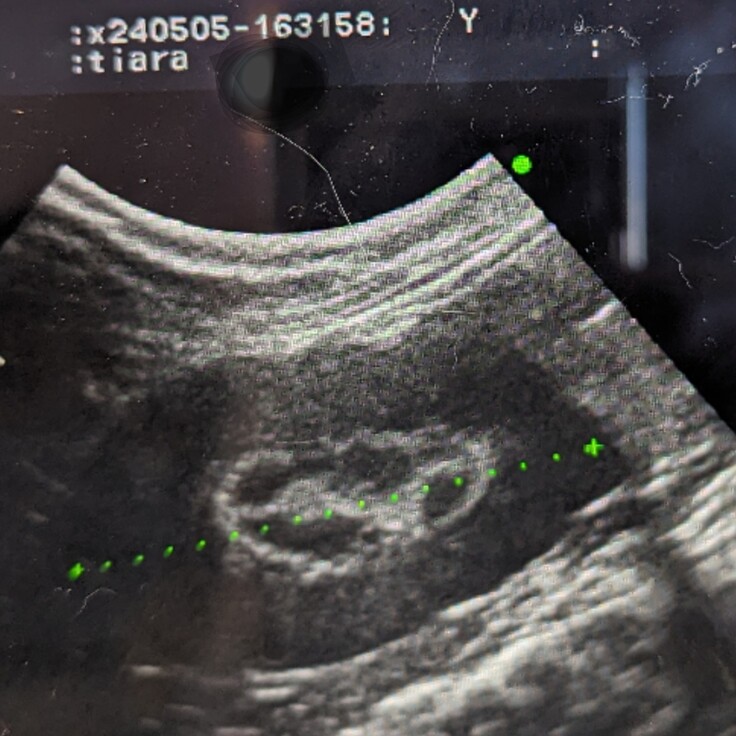

定期検診に行ってきました🏥

昨日になりますが、約半年ぶりの定期検診に行ってきました。

今回は半年ぶりなので、より細かい検査をしました。一部外注検査のため全てではありませんが概ね現状維持で問題はありませんでした。

腎臓のリムサインは素人目でも分かるくらいに少し薄くなっていました。ただ検査中にティアラが暴れたので上手く撮れなかったことも否定できないそうです。次の検査でも薄いようなら、もう消えることがないだろうと諦めていたリムサインに少しの光が見えたことになります✨

血液検査でも腎臓に問題はなかったので安心しました。